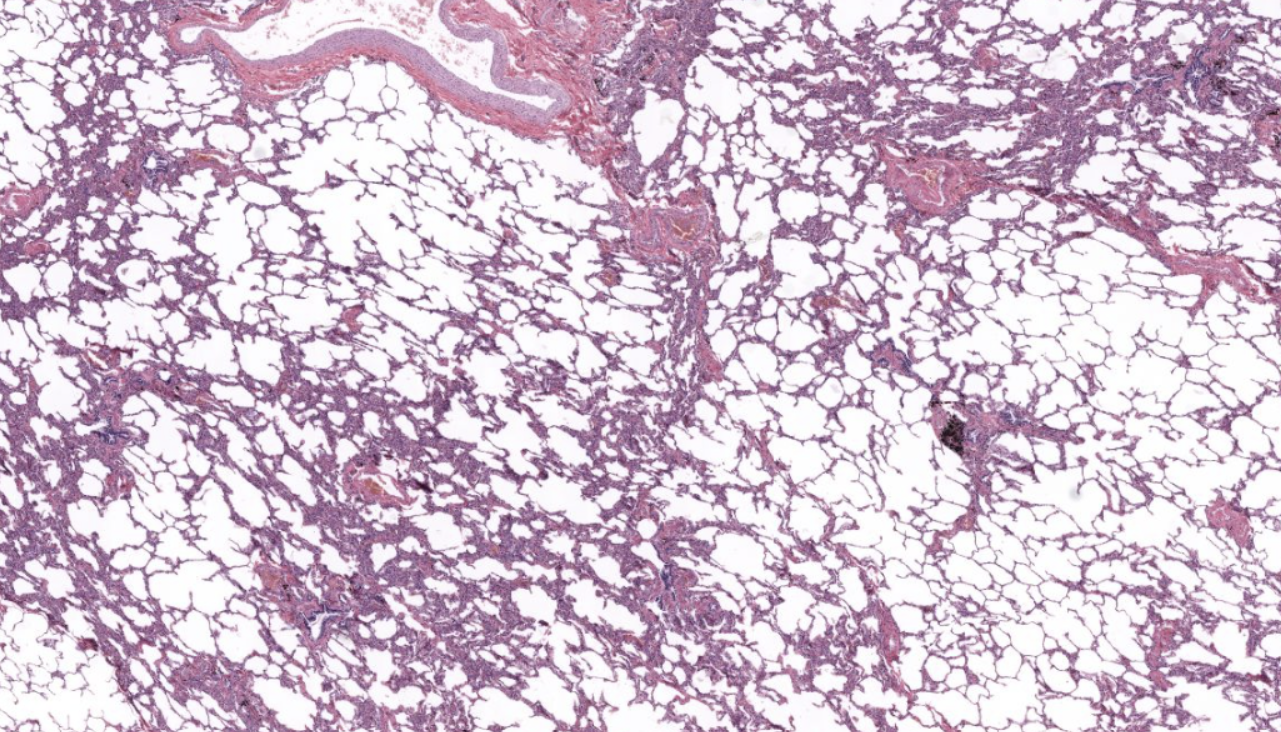

Lung tissue

NOTICE: THE OPEN SPACE OF THE ALVEOLI